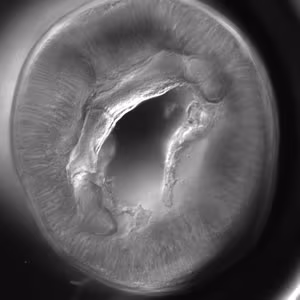

Anterior end of Pseudoterranova sp. The red arrow indicates the intestinal cecum.

Diagnosis can be made by gastroscopic examination during which the larvae are visualized and removed, or by histopathologic examination of tissue removed at biopsy or during surgery. Worms may be coughed up and brought in by patients.

Genus-level identification is not required for patient management but may be accomplished by examination of digestive structures and lateral chords. Examination of esophageal and intestinal morphology usually requires clearing in lactophenol.